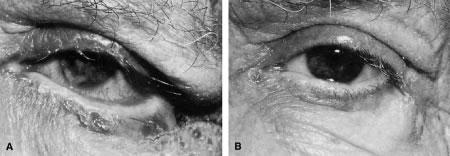

Ectropion and entropion share similar anatomic features. The most common predisposing anatomic factors for lower lid malpositions are horizontal eyelid laxity and weakness or defects of the lower lid retractors. The general weakness of the eyelid is caused by a weakness of the medial and lateral canthal tendons, permitting horizontal eyelid laxity.4 As such, it is best to consider lower eyelid laxity as resulting from laxity of the tarsoligamentous sling or support for the eyelid. The anatomic weakness can be demonstrated by the snap test. Downward retraction is exerted on the lower lid, pulling it away from the globe. On relapse, the lower lid should snap back against the globe spontaneously. Failure of the eyelid to snap back against the globe with a single blink indicates excessive laxity of the tarsoligamentous sling.

The lower eyelid retractors may be weakened or may actually become disinserted from the inferior tarsal border. Weakness or defect of the lower eyelid retractors creates in an instability of the inferior tarsal border that is manifested clinically as ectropion or entropion.